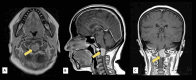

Figure 2

Figure 2. T1-weighted, post-gadolinium cranial magnetic resonance (MR) imaging in (A) axial, (B) sagittal, and (C) coronal views showing a well circumscribed, contrast-enhancing extra-axial mass lesion measuring approximately 2.9x2.1x3.1 cm (CCxWxAP) within the spinal canal at the level of C1-C2, extending from the inferior clivus to the level of the C2 vertebra (arrow)

CC: Craniocaudal; W: Width; AP: Anteroposterior